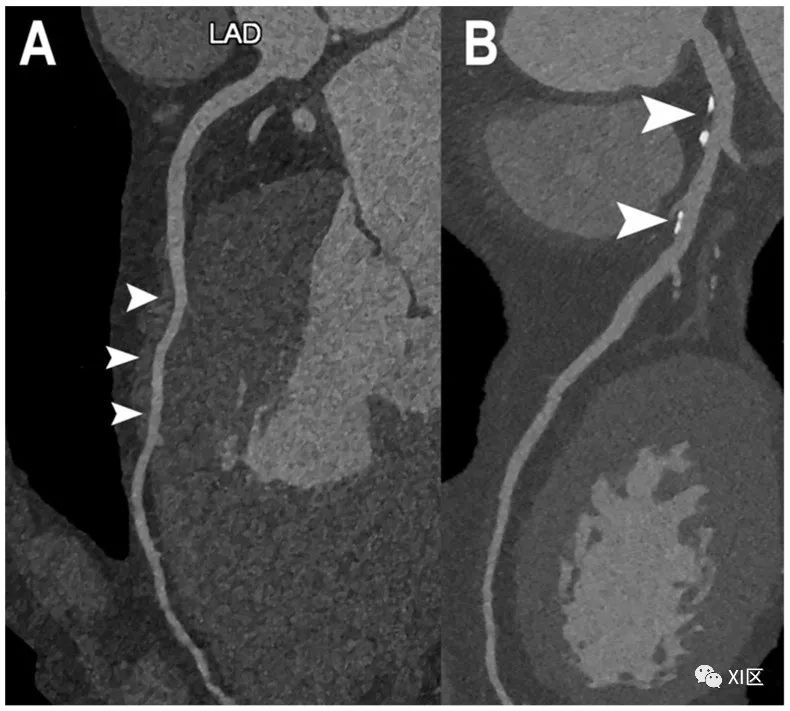

正常和非阻塞性CAD的心脏PCCT示例。图中显示了左前降支(LAD;(A,B))的两个示例。在(A)中,左前降支完全正常,没有任何CAD迹象;唯一的发现是中段((A);箭头)的心内膜走向较深((A))。在(B)中,至少有两个以钙化为主的动脉粥样硬化斑块((B);箭头),但冠状动脉管腔没有任何明显阻塞迹象。使用PCCT进行成像的特别之处在于,这种非常高的细节和空间分辨率是通过标准成像方案获得的,而且不需要高辐射剂量。